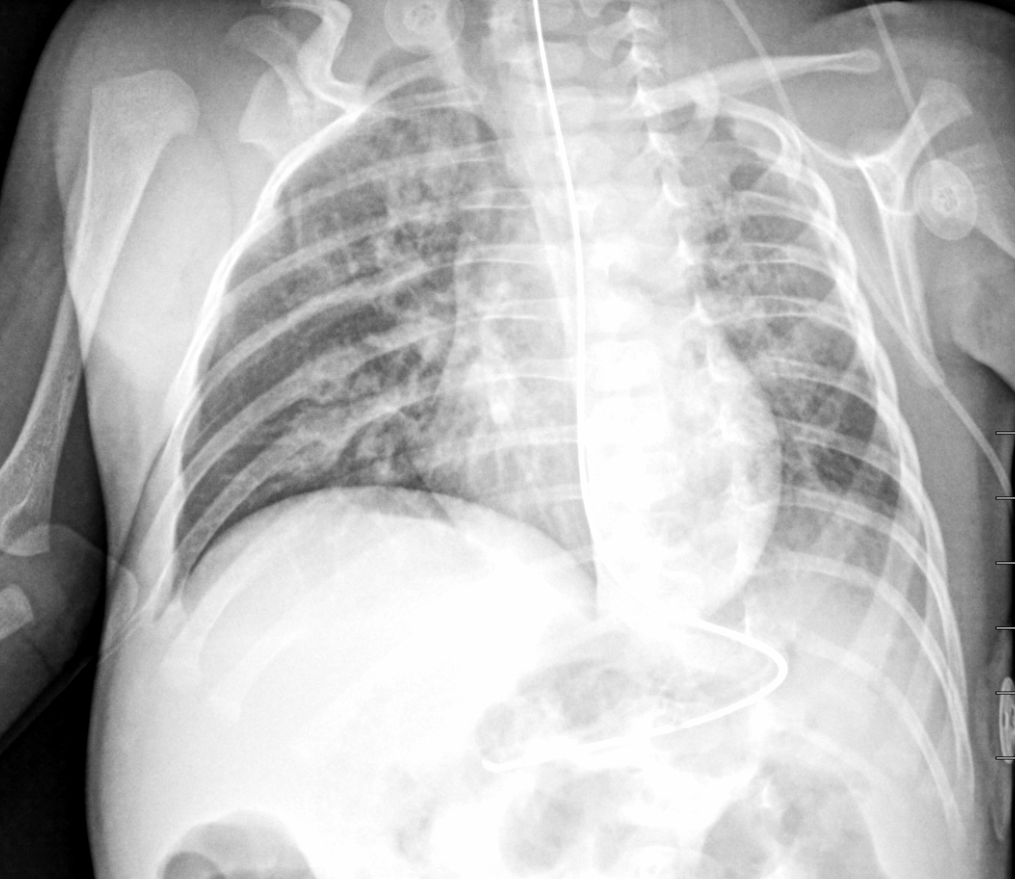

Info Images Findings Impression Reco/Acuity Case Images View Images / Launch Visage Case Notes History 2-month-old presents with decreased right arm movement, increased fussiness, and increased sleepiness for 2 days. Suspected non-accidental trauma. Exam Skeletal survey Prior Study none Dicom View Reference Material

Section 1 Submit Findings CB1550 Findings Skeletal Survey - Technique Check Skull AP/Lat Yes No Cervical and Thoracolumbar spine Yes No Chest X-Ray Yes No Ribs – Left/Right Oblique Yes No Abdominal X-Ray Yes No Pelvis with both hips Yes No Bilateral Humerus, Forearm, Hand Yes No Bilateral Femur, Tibia/fibula, feet Yes No Any additional lateral views of the extremities Yes No The exam is over or under penetrated. Yes No The exam may or may not be limited by overlying structures or soft tissues, body habitus, patient positioning, support devices, or motion. Yes No The area of concern is indicated by the patient, technologist, or care provider. Yes No The area of concern is included on the exam. Yes No Soft Tissues There is soft tissue swelling, indistinctness of fat/muscle planes, gas, or laceration in the area of clinical concern. Yes No There is an effusion, fat pad displacement, or fat fluid level. Yes No There is a radiodense or lucent foreign body. Yes No There are other densities, calcifications, post-surgical changes, or support devices in the soft tissues. Yes No Any support lines/tubes. Yes No Bone There is a break or interruption of the continuity of the cortical or cancellous bone. Yes No There is overriding of the trabeculae with apparent sclerosis. Yes No There is displacement of a fracture fragment. Yes No There is bowing of the bone in addition to the fracture at the apex of the bowed bone concerning for the greenstick. Yes No There is a spiral fracture of the leg concerning for toddler’s fracture. Yes No There is abnormal angulation or bulging of the cortical surface relative to the normal cortex which could be from a buckle or torus fracture. Yes No There is a displaced fragment which may be from avulsion by a tendon, ligament, or joint capsule or from a comminuted or other fracture. Yes No The stress trabeculae or other trabeculae of the cancellous bone are interrupted or otherwise abnormal. Yes No There is subperiosteal or endosteal reaction which could indicate a healing or subacute fracture or other abnormality. Yes No There is hard/soft callus formation. Yes No There is remodeling of the bone. Yes No There is a corner fracture or metaphyseal lesion that could be from nonaccidental trauma. Yes No There are multiple fractures of different ages. Yes No There are vertebral body/spinous process fractures. Yes No There are rib fractures. Location - posterior or lateral. Yes No There is scapular/sternal fracture. Yes No There are fractures of the digits. Yes No There are wormian bones. Yes No There are intrasutural bones. Yes No There is metaphyseal abnormality (lucencies, increased density, erosion) which may be from something other than injury such as stress, metabolic disease (e.g. rickets with loss or distortion of the zone of the provisional calcification), neoplasm (e.g. leukemia), heavy metals, inflammation, or infection. Yes No There are metaphyseal spurs. Yes No There are bony deformities involving multiple bones. Yes No The bones are gracile. Yes No There are non-healing fractures. Yes No There is/are focal or multifocal lytic/lucent, blastic/sclerotic or mixed density lesion(s) or other abnormality. Yes No Overall bone density is increased or decreased with or without thinning or thickening of the cortical or cancellous bone. Yes No Growth plates, ossification centers, apophyses The growth plate(s) is/are abnormal. Yes No There is widening of the physis from a fracture with or without displacement of the epiphysis (Salter-Harris I). Yes No There is a fracture through the physis which then extends into the metaphysis with or without angulation or displacement (S-H II). Yes No There is a fracture through the physis which then extends into the epiphysis and is intra-articular, with or without angulation or displacement (S-H III). Yes No There is a fracture through the metaphysis, physis, and epiphysis which extends into the joint space with or without angulation or displacement (S-H IV). Yes No There is narrowing of the physis from a compression fracture (S-H V). Yes No The apophysis, epicondyle, secondary ossification center, or accessory ossicle is displaced or otherwise abnormal. Yes No The ossification centers are underdeveloped. Yes No Joints and alignment There is an effusion, fat pad displacement, or fat fluid level. Yes No The epiphysis or subchondral bone is fractured, interrupted, flattened, compressed, impacted, displaced, or otherwise abnormal. Yes No There is an intra-articular loose body or chondrocalcinosis. Yes No The joint is widened, narrowed, dislocated, malaligned, or incongruent. Yes No There is pseudoarthrosis. Yes No Other findings There are developmental changes or other anatomic variants or other existing conditions that may or may not be contributing to symptoms which can or should be further evaluated non-emergently or are otherwise incidental. Yes No The remainder of the exam is abnormal for age. Yes No The lungs show focal airspace opacity. Yes No There is pneumothorax. Yes No There is organomegaly. Yes No There is intra-abdominal calcification. Yes No There is displacement of the bowel loops. Yes No There is free intraperitoneal air. Yes No The bowel loops are dilated/obstructed. Yes No There is paraspinal soft tissue abnormality. Yes No